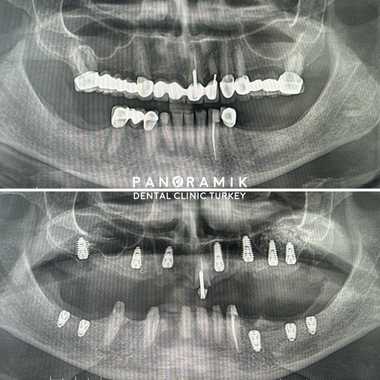

What Is a Sinus Lifting?

This is a dental operation performed to increase the volume of bone tissue in the upper jaw. During implant treatment in case of insufficient bone tissue in the area of the upper molars and premolars, patients need to have  an operation called sinus lifting. There are two types of sinus lifting methods: open and closed.

Open (lateral) sinus lifting: It is a mini-surgical operation performed with local anesthesia in cases where the bone height is below 4 millimeters.

Closed (internal) sinus lifting: It is applied in cases where the bone height is between 4mm-7mm. The floor of the sinus is raised using a special instrument called an osteotome and filled with bone graft. This procedure is performed using local anesthesia. Sinus lifting operations are painless procedures that take 30-60 minutes. İf there is enough bone tissue, implants can be installed in the same session.